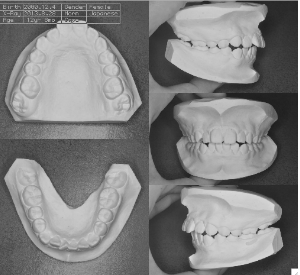

ステップ5.精密検査

口腔内写真,レントゲン

(必要に応じてCT)

印象(歯型)採得

装置装着前

装置装着後